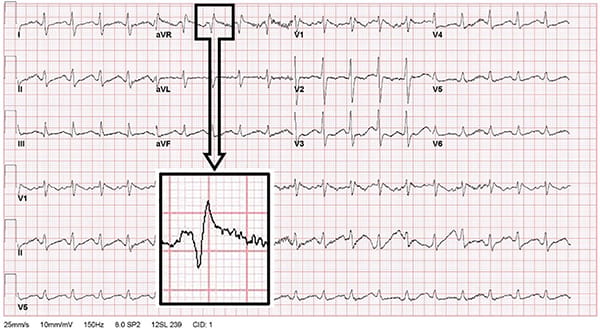

2b C-LD 1. The effectiveness of artifact-filtering algorithms for analysis of electrocardiogram rhythms during chest compressions for adults in cardiac arrest has not been established.